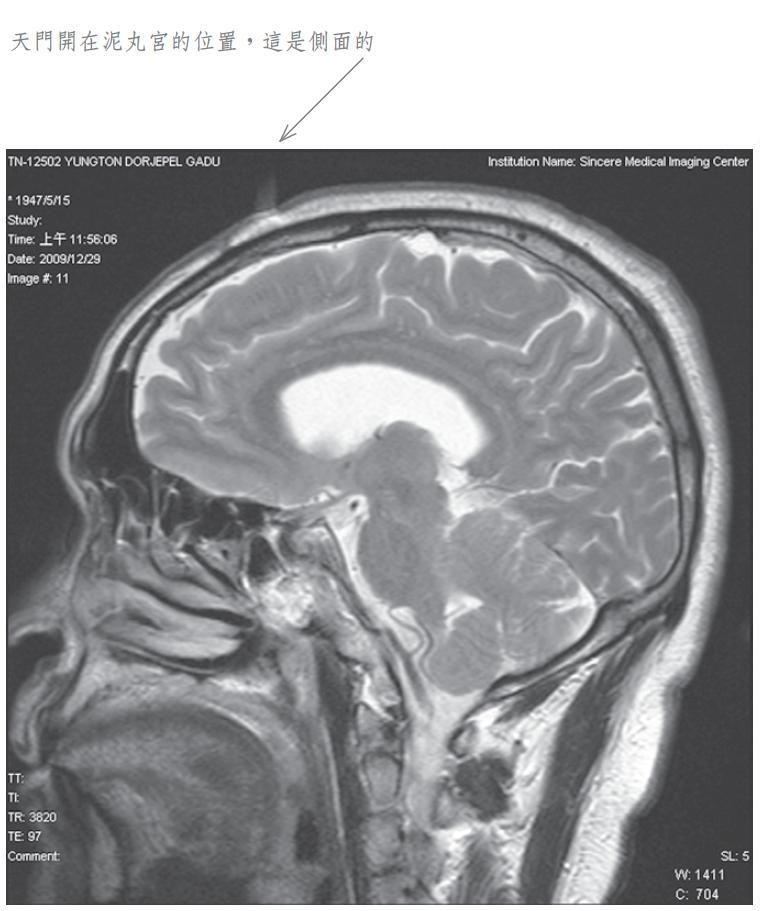

当我将此种修法中发生之觉受禀报佛陀师父时, 佛陀师父又为我传了秘密口诀。经过一段时日, 佛陀师父在公开开示的法音带中,才提到我曾经修法达到化身境的初级,即是素化身的意思。为了让众生明了佛法的伟大,事隔多年之后,我特别于二零零九年十二月廿九日,到中心综合医院安排磁振造影(MRI)头部的摄影检查,结果发现泥丸宫的部位出现一个1.5公分宽深的开口,同时拍下了有一股神识出气冲出头部的实况。负责检查的医生非常惊讶称奇,但无法解释其原因,因而将它归因于非人之所为。我其实非常清楚,我的神识化身本来就是从这里出入的,以下是在医院MRI检查的扫瞄片。